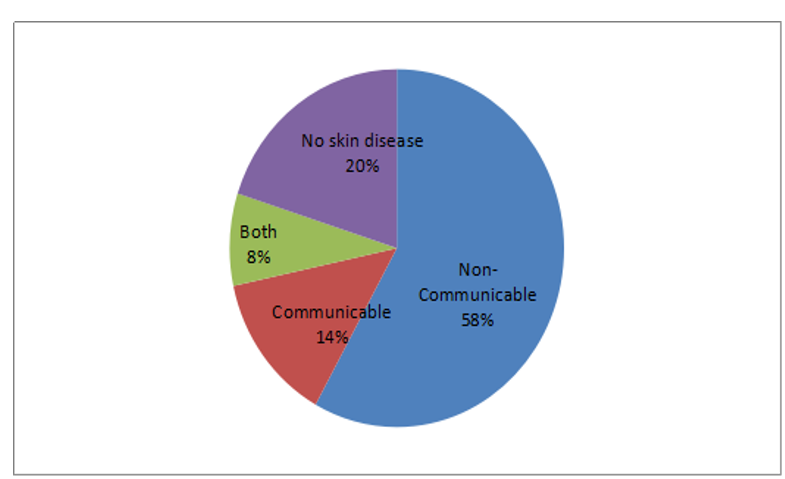

The sustainable livelihood framework is the most insightful and commonly used framework despite its limitations in assessing vulnerability of rural livelihoods to climate change. Most of the vulnerability assessments account for the livelihoods and factors that either influence or constrain in the adaptation [2]. This framework is also motivated from sustainable livelihood framework, which basically explains the natural and anthropogenic causes triggered climate risks and vulnerabilities impacting the livelihoods of the people. Over exploitation of available livelihood resources and increased anthropogenic interventions further aggravated the climate risks and vulnerabilities at the household and community level. In contrary, increased climatic risks and vulnerabilities further destroyed the resources [1]. In that sense, these livelihood resources can also be considered as the factors which either support the adaptation or further increase the climate risks and vulnerabilities. Adaptation is one of options to reduce the impacts of climate change through adaptation choices/strategies and adaptation policies/plans. Multiple factors influence these adaptation strategies/choices and policies/plans either enhancing or restraining it in the process. The current study mainly concentrated on these factors at the national and local levels including the household level in the study sites. The possible factors are included in the framework. All of these listed factors may not be applicable in this study and analysis (Figure 1). The current study concentrates on analyzing the factors at the local level particularly focusing on household level factors such as age, gender, education, occupation, ethnicity, family size, economically active members per household, land holding size at the household level through questionnaire survey. Age, gender, ethnicity and family size are included in the social factors, whereas occupation and land holding size are included in the economic factors since these factors assist in the economy of the household. Likewise, the economically active members per household is considered as the human capital.

Figure 1: The conceptual framework of the research.